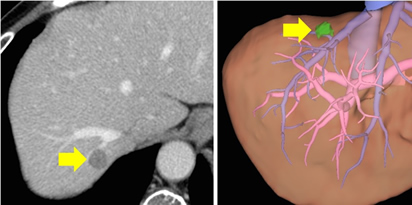

左上図は転移性肝臓がんの手術前のCTですが、腫瘍(黄色矢印)は血管に近いものの肝臓表面近くに位置しており、比較的容易に手術が可能と考えられます。3D構築像(右上図)でみても肝臓表面の小さな腫瘍であることがわかります。実際の手術では、腫瘍を含めた部分切除という術式が選択されました。